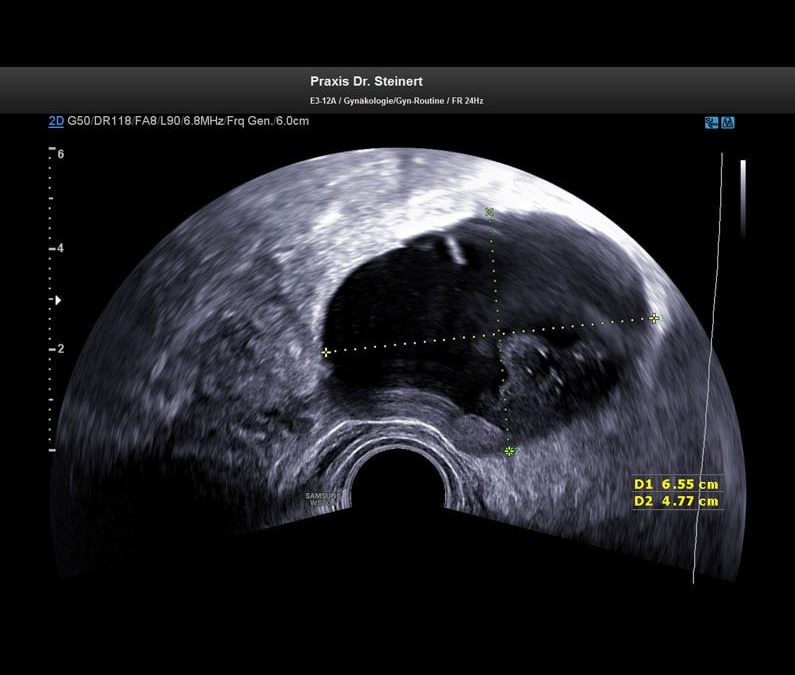

ultraschall-bild2-gutartiger-tumor